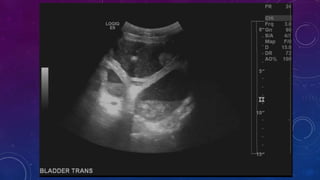

SEVERELY DILATED URINARY BLADDER WITH

DIVERTICULAE AND CALCULI